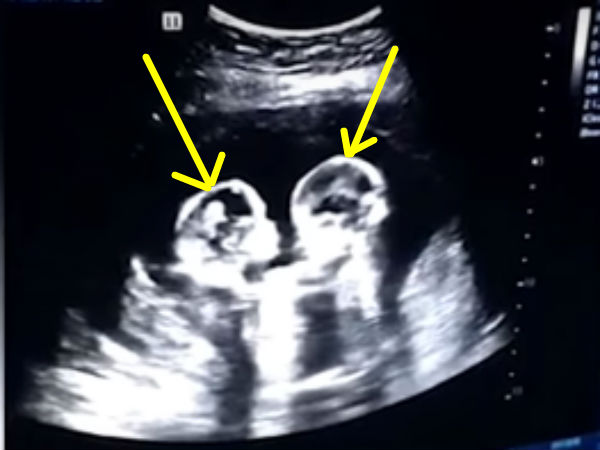

இந்நிலையில், நிறைமாத கர்ப்பிணியாக இவர் இருந்தபோது ஆஸ்பத்திரிக்கு செக்-அப்புக்காக சென்றிருக்கிறார். அங்கு அவருக்கு ஸ்கேன் செய்து பார்க்கப்பட்டது.

அப்போது கருப்பையில் இருந்த இரண்டு குந்தைகளும் சண்டை போட்டு கொண்டு விளையாடி உள்ளன. முழு கரு வளர்ந்திருந்த நிலையில் குழந்தையின் உருவம் கர்ப்பப்பையில் தெளிவாக தெரிகிறது.

குழந்தைகளின் இரு மண்டைகளும் முட்டிக் கொள்வதும், மோதிக் கொள்வதும், சில சமயம் கைகளால் தள்ளி கொள்வதும் என ஒரே சண்டையாக இருக்கிறது. இது சண்டையா, விளையாட்டா, அல்லது விளையாட்டுக்கு சண்டையா என தெரியவில்லை. இதை பார்த்ததும் குழந்தைகளின் பெற்றோருக்கு சந்தோஷம் தாங்கவில்லை.